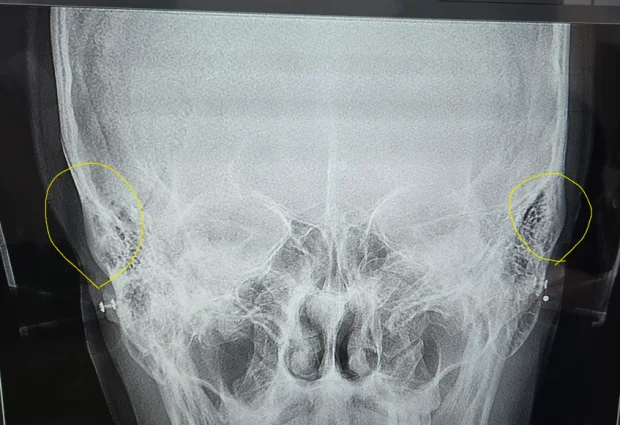

2025-10-04 03:33:51CT사진 상 이부위가 어느뼈인가요?

광대 뼈 위쪽에 튀어나온 뼈가 무슨뼈일까요

Dr.s Diagnosis안녕하세요. CT 사진에 대한 질문 주셨네요. 사진을 바탕으로 자세히 설명드리겠습니다.

CT 사진 판독:

* 광대뼈 위쪽 튀어나온 뼈: 사진상으로는 명확하게 특정 뼈를 지칭하기는 어렵지만, 광대뼈 위쪽에 튀어나온 뼈는 관골궁(Zygomatic arch) 의 일부일 가능성이 높습니다. 관골궁은 광대뼈에서 시작하여 측두골까지 연결되는 활 모양의 뼈 구조입니다.

관골궁 관련 추가 설명:

* 역할: 관골궁은 얼굴의 폭을 결정하고 씹는 근육(저작근)의 부착 지점 역할을 합니다. 또한, 얼굴의 외형을 형성하는 데 중요한 역할을 합니다.

* 손상: 외부 충격 등으로 관골궁이 골절될 수 있으며, 이 경우 얼굴의 변형, 통증, 씹는 기능 장애 등이 발생할 수 있습니다.